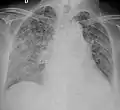

Tuberculosis of the lungs

Testing for miliary tuberculosis is conducted in a similar manner as for other forms of tuberculosis, although a number of tests must be conducted on a patient to confirm diagnosis.[4] Tests include chest x-ray, sputum culture, bronchoscopy, open lung biopsy, head CT/MRI, blood cultures, fundoscopy, and electrocardiography.[10] The tuberculosis (TB) blood test, also called an Interferon Gamma Release Assay or IGRA, is a way to diagnose latent TB. A variety of neurological complications have been noted in miliary tuberculosis patients—tuberculous meningitis and cerebral tuberculomas being the most frequent. However, a majority of patients improve following antituberculous treatment. Rarely lymphangitic spread of lung cancer could mimic miliary pattern of tuberculosis on regular chest X-ray. [15]

A case of miliary tuberculosis in an 82-year-old woman: